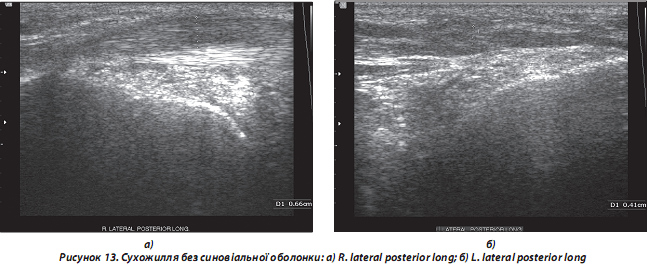

б) гострий тендиніт:

— сухожилля без СО: потовщені, ехогенність останніх знижена локально/дифузно. Ехоструктура неоднорідна, з наявністю дрібних гіпоехогенних ділянок, що нагадують мікророзриви, значним посиленням кровотоку за ходом сухожильних волокон при поздовжньому скануванні (рис. 13);